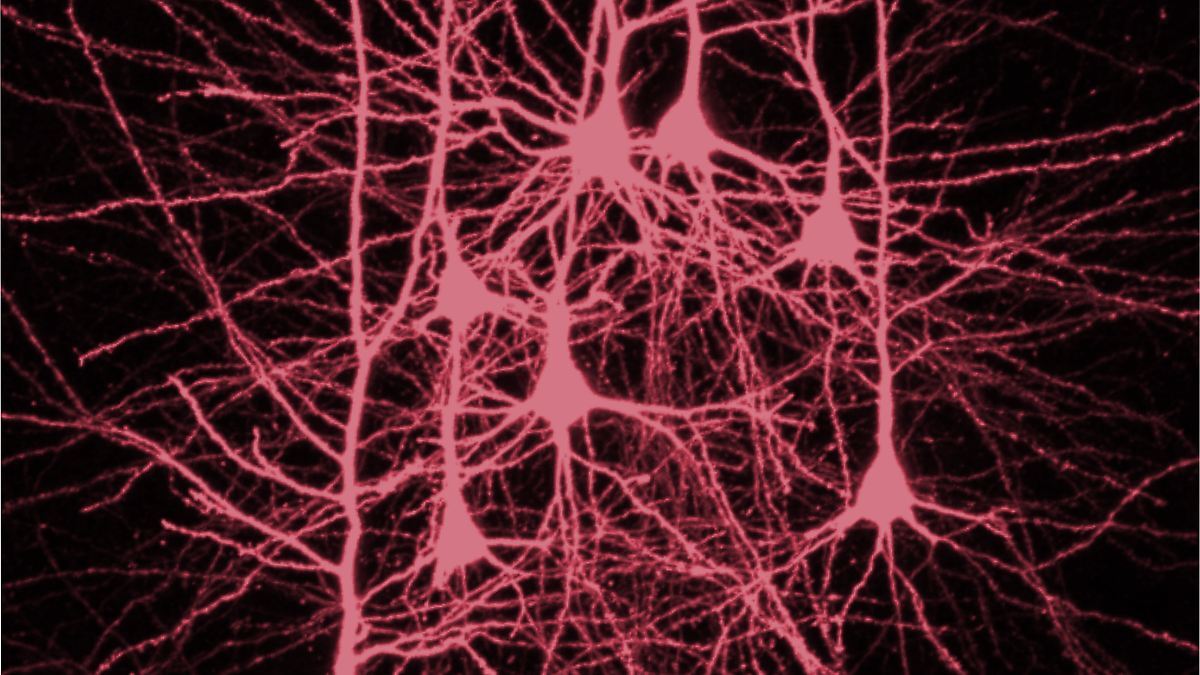

Studie enthüllt: Rechter Stirnlappen ist das Zentrum des logischen Denkens. 247 Patienten mit Hirnschäden zeigten 15% mehr Denkfehler bei Schädigungen in dieser Region. #Neurowissenschaft #Gehirnforschung https://winfuture.de/news,150378.html?utm_source=Mastodon&utm_medium=ManualStatus&utm_campaign=SocialMedia